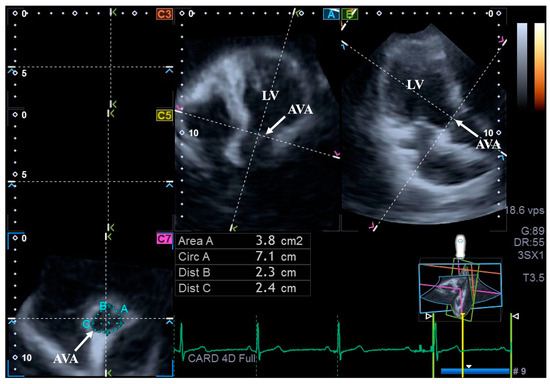

For the assessment of AVA dimensions, longitudinal planes on the AP4CH and AP2CH long-axis views were optimized by tilting these planes so that they were aligned to be parallel to the center line of the aortic root. Then, in the C7 cross-sectional view, the examination plane was aligned perpendicular to the longitudinal plane, to the AVA. These alignments have to be performed carefully to ensure that this C7 plane is perpendicular to the center line and to make measurements on the real AVA, not on the LV outflow tract or on the Valsalva. With this method, the following AVA characteristics were assessed: maximum and minimum AVA diameters (Dmax and Dmin, respectively) and areas (A) and perimeters (P) in the end-diastole (ED) and end-systole (ES) [8] (Figure 2).

Figure 2.

Assessment of the aortic valve annular dimensions by three-dimensional speckle-tracking echocardiography. Abbreviations: LV = left ventricle; AVA = aortic valve annulus; Area = AVA area; Circ = AVA perimeter; Dist B = maximum AVA diameter; Dist C = minimum AVA diameter.